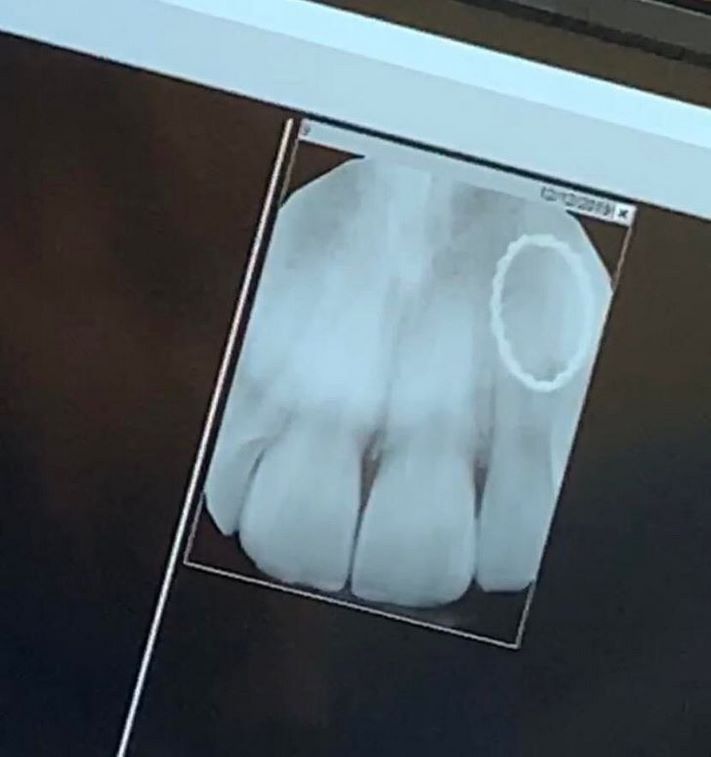

Երեխայի ծնոտը, որի մեջ «թաքնված» են դեռ չծակած սեղանատամները

Եվ ահա, թե ինչպես է հիմնական ատամը «ճնշում» կաթնայինին` զբաղեցնելով նրա տեղը